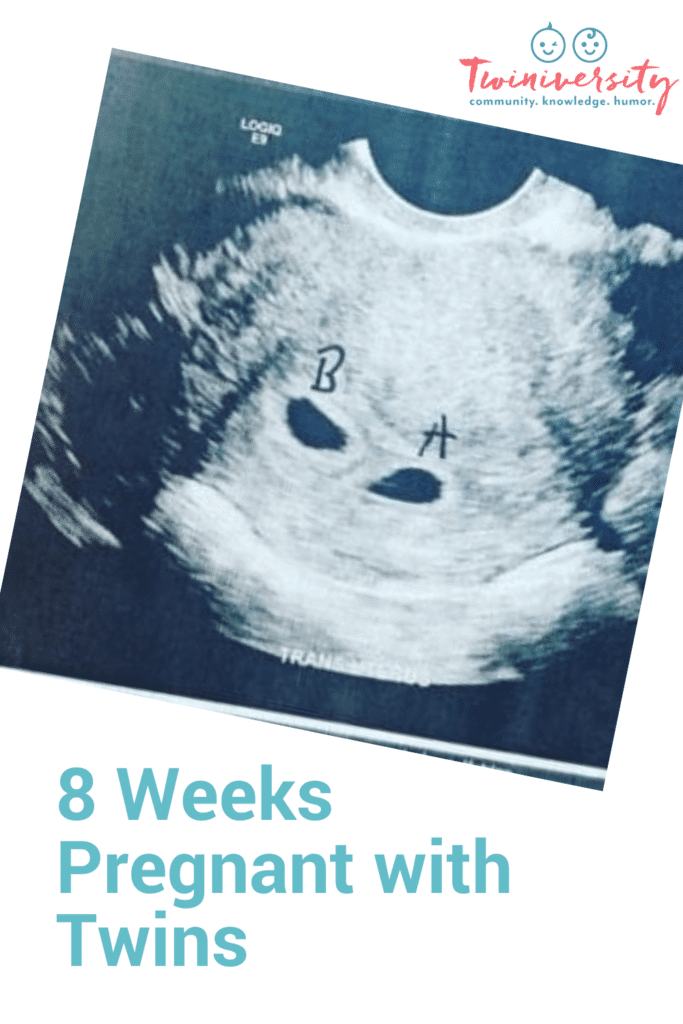

REMINDER: Don’t forget to take a belly shot! 8 week sonogram

Ultrasound Photos – 8 Week Sonogram

8 week sonogra